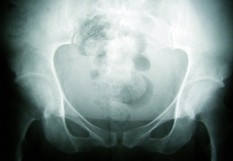

"Les inhibiteurs du checkpoint immunitaire (anti-PD-1, anti-PD-L1) ont changé radicalement le pronostic de plusieurs cancers, dont le mélanome métastatique", s’est félicité le Pr Thierry Schaeverbeke, chef de service de rhumatologie au CHU de Bordeaux. Le prix à payer à cette rupture de la tolérance immunitaire est la survenue d’effets secondaires, dont les plus fréquents sont dermatologiques (érythème, vitiligo), gastro-intestinaux (colites parfois sévères), endocrinologiques (hypophysites, thyroïdites), neurologiques : syndrome de Guillain-Barré. Cependant, ces traitements peuvent aussi provoquer des complications rhumatologiques de tous types : polyarthrites de type « PR », en général avec syndrome inflammatoire biologique modéré, pseudo-polyarthrites rhizoméliques, rhumatismes psoriasiques, myosites, arthralgies, myalgies, tendinopathies... Dans une série de 648 patients suivis au CHU de Bordeaux, recevant une immunothérapie, 43 % des malades ont ainsi présenté un effet secondaire, le plus souvent dermatologique (162 patients), gastro-entérologique (n = 81), ou endocrinologique (n = 67), mais également parfois rhumatologique (n = 49). L’étude récente de M. Kostine, et al.*, a montré que ces manifestations rhumatologiques, qui surviennent en moyenne après 70 jours d’exposition, témoignent d’une réponse au traitement immunologique (85,7% de patients répondeurs en leur présence contre 35,3% en leur absence ; p < 0,0001). Ce meilleur taux de réponse chez les patients avec un effet secondaire a aussi été constaté dans la cohorte bordelaise. "Chez ces patients, le traitement par immunothérapie peut être maintenu le plus souvent", a indiqué le Pr Schaeverbeke. “Les pathologies articulaires répondront en général à une corticothérapie. Plus rarement, le recours à un traitement de fond systémique : méthotrexate ou anti-TNF ou anti-IL 6 peut être nécessaire. Mais, les myosites peuvent être plus sévères".